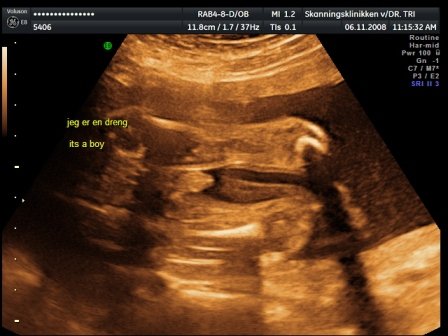

kaptunk félórás dvd-t a vizsgálatról, kétoldalas leírást a bébiről, 3 fekete-fehér képet és egy színeset kinyomtatva, és 23-at egy másik dvd-n:D tök rendes volt a csaj... de a kis drágám nagyon dugdossa az arcocskáját.. mindent megmutat, de az arca az magánügy úgy gondolja :D azért elég makacsak voltunk úgyhogy nagy nehezen sikerált egy profil :D azt mondta a dokinő hogy nagyon nagyon aktív bébi :D és teljes bizonysággal kistökös :D:D:D Kép bébi 4D Kép a kis tökös Kép kezek-lábak